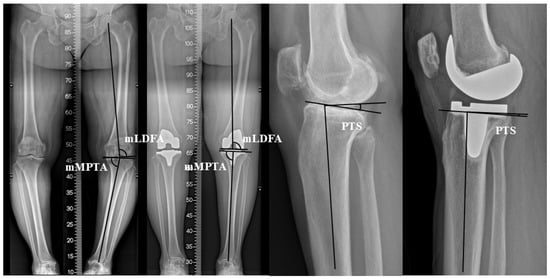

The Degree of Joint Line Obliquity Change Is Not Associated with Patient Preference in Bilateral Posterior-Stabilized Total Knee Arthroplasties

Objectives: To evaluate patient reference in paired bilateral posterior stabilized (PS) total knee arthroplasties (TKAs) with significantly different degrees of joint line obliquity (JLO) change. Methods: A retrospective review was conducted on 128 patients who underwent paired bilateral PS TKAs, with greater and [...] Read more.

Objectives: To evaluate patient reference in paired bilateral posterior stabilized (PS) total knee arthroplasties (TKAs) with significantly different degrees of joint line obliquity (JLO) change. Methods: A retrospective review was conducted on 128 patients who underwent paired bilateral PS TKAs, with greater and smaller JLO changes (G-ΔJLO and S-ΔJLO knees; a side-to-side difference in JLO change >3° between G-ΔJLO and S-ΔJLO knees). The mean follow-up period was 3.9 years (minimum 2 years). Radiographic changes in JLO were measured according to the Coronal Plane Alignment of the Knee (CPAK) classification. Maintenance of the CPAK type and JLO direction (apex distal, neutral, and apex proximal) was investigated. Clinically, the preferred TKA out of greater and smaller JLO changes was investigated. The Hospital for Special Surgery and Western Ontario and McMaster Universities Osteoarthritis Index were evaluated. Results: The average JLO change was 10.5° in the G-ΔJLO knees and 5.5° in the S-ΔJLO knees (p < 0.001). The CPAK type and JLO direction was better maintained in the S-ΔJLO knees (p < 0.001, respectively). Regarding preference, 40 patients (31.2%) were satisfied with bilateral TKAs without a specific preference, while 44 patients (34.3%) preferred TKAs of the G-ΔJLO knee and 44 patients (34.3%) preferred the S-ΔJLO knee (p = 1.000). No significant differences were found in the patient reported outcomes between the G- and S-ΔJLO knees. Conclusions: The degree of joint line obliquity change was not associated with patient preference in bilateral PS TKAs. JLO preservation may not be a critical determinant of patient preference in PS TKA. Full article